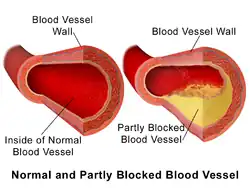

| Normal and partially blocked/occluded blood vessel | |

A coronary occlusion, or coronary artery disease, is the partial or complete obstruction of blood flow in a coronary artery. This condition was first discussed in 1910 by Sir William Osler.[1] This condition slows or blocks the supply of oxygen-rich blood to the heart.[2] This condition can lead to myocardial ischemia[2] and if untreated, may cause a heart attack and heart failure.[3] It is the most common form of cardiovascular disease, and is the leading cause of death in the United States, affecting 18 million adults.[4]

Coronary occlusion is caused by the buildup of fats, cholesterol and other substances in and on the walls of the hearts arteries.[6] As plaque builds up, the arteries narrow.[7] Plaque often starts building up during childhood and is heavily influenced by genetics, but also lifestyle and high blood cholesterol.[7] This condition is referred to as atherosclerosis.[6] The buildup on the walls of the hearts arteries is referred to as plaque. Plaque causes arteries to narrow and block blood flow.[6]

Coronary occlusion is caused by plaque inside of the blood vessels that direct oxygen rich blood to the heart.[8] Plaque is caused by fatty deposits and scar tissue that cling to the walls of coronary arteries.[9] The development of plaque takes years and leads to stenosis of the coronary arteries and progressively reduces blood flow.[8] Due to the slower development of this condition, the body will adapt and create small blood vessels that circumvent the blockage.[8] The small blood vessels form a natural bypass of the blockage, but often do not supply enough blood to meet an increased demand when stressors are applied like exercise.[8]